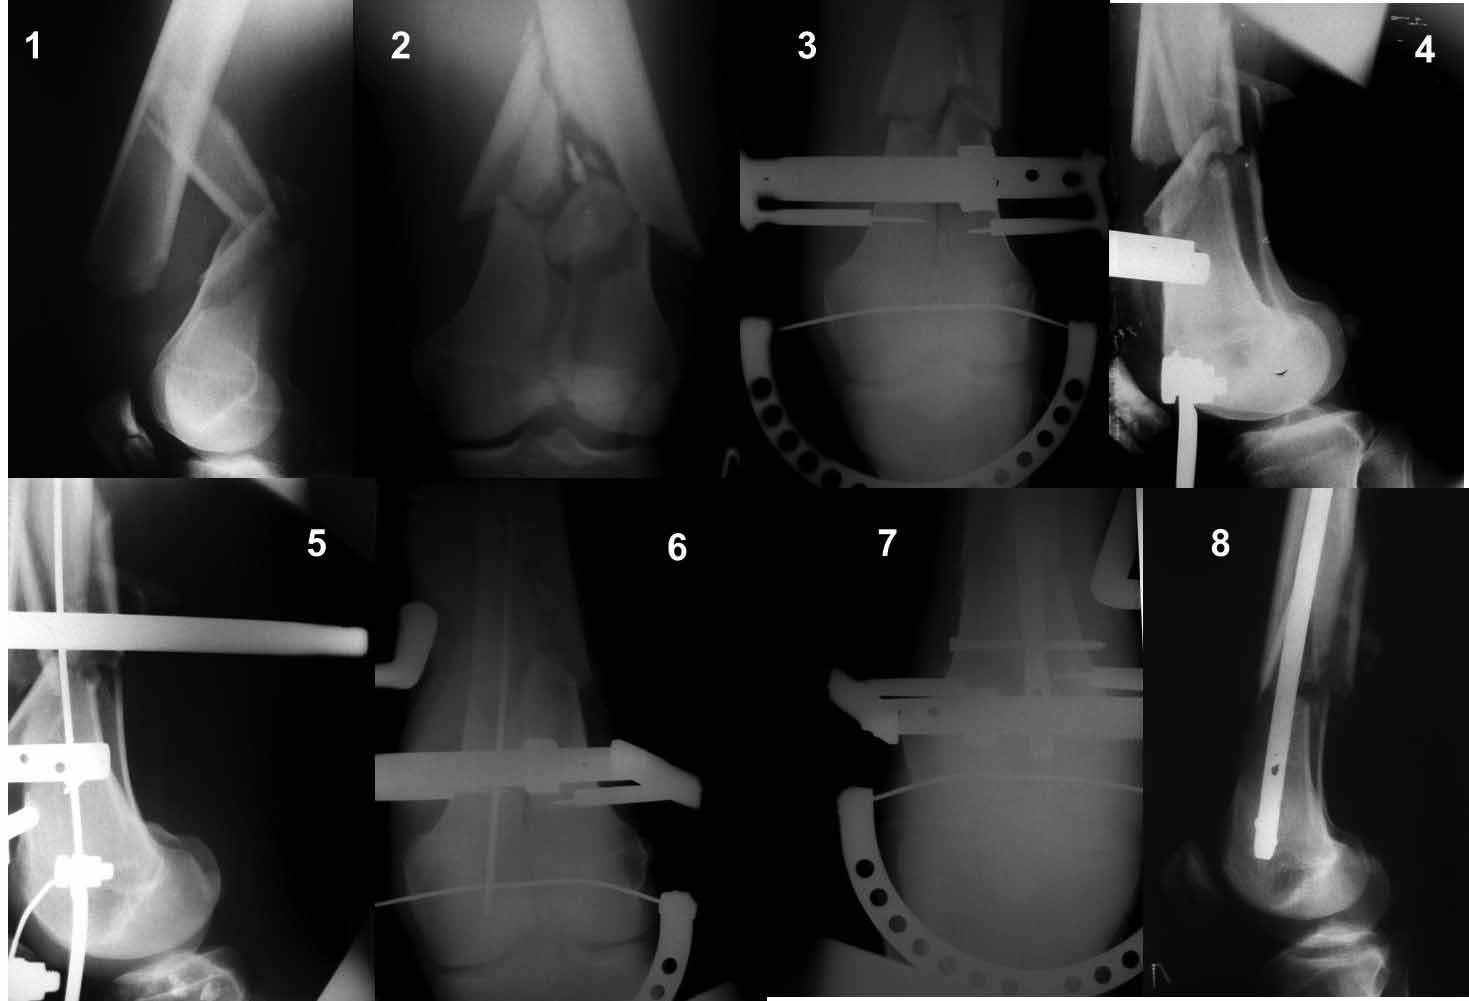

Ну зачем же так. Всё-таки считается "золотым стандартом". Во вложенном файле коллаж из сохранившихся фотографий одной из операций. Всё сделано закрыто и без ЭОПа.